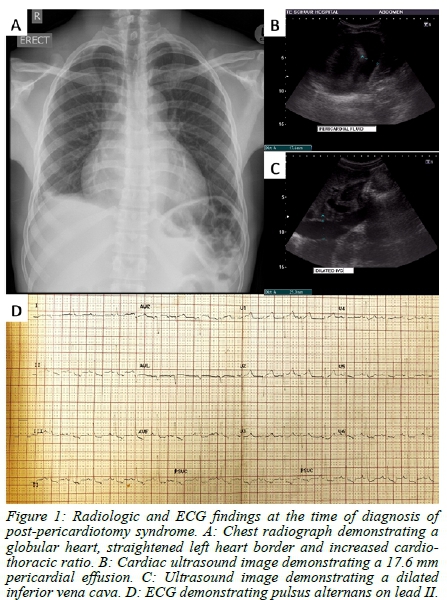

Four weeks later, the patient re-presented at our trauma unit with complaints of abdominal pain, pleuritic chest pain and shortness of breath. He was apyrexial, blood pressure was 114/91 mmHg with a pulse rate of 93 bpm. Respiratory rate was 16 breaths per minute. His neck veins were distended, and heart sounds were soft. His liver was enlarged, tender and palpable below the right costal margin. Chest radiograph revealed a globular heart shadow with increased cardiothoracic ratio (CTR) of 0.60 (Figure 1A). ECG displayed features of pulsus alternans (Figure 1D) and cardiac US showed a 17.6 mm pericardial effusion (Figure 1B) with a dilated, non-collapsible inferior vena cava (IVC) (Figure 1C). A diagnosis of post-pericardiotomy syndrome (PPS) was made, and the patient was admitted to the ward for nonsteroidal anti-inflammatory drug (NSAID) therapy. The following morning, he had persistently distended neck veins, but the chest pain felt better, so we continued NSAID treatment and close monitoring in the ward. Three days later, the patient complained of weakness and had a single episode of vomiting. He remained apyrexial and his vital signs remained stable. Repeat chest radiograph demonstrated a persistently globular heart, with a further increased CTR of 0.62. A few hours later, the patient was found cold and unresponsive with agonal breathing in the ward. He was found to be pulseless and CPR was commenced immediately, while awaiting equipment to perform a resuscitative thoracotomy. Deep endobronchial intubation was performed, so as to enter the right main bronchus and collapse the left lung, and a left anterolateral thoracotomy was performed at the bedside. Furthermore, no medication was required to perform the intubation or the thoracotomy. The bulging pericardial sac was noted, and this was opened using the same blade that we performed the thoracotomy with. A large gush of fluid estimated between 400-500 ml was drained immediately, and open cardiac massage was commenced, with almost immediate return of spontaneous cardiac activity and circulation. By this time, the patient had had three doses of intravenous adrenaline.